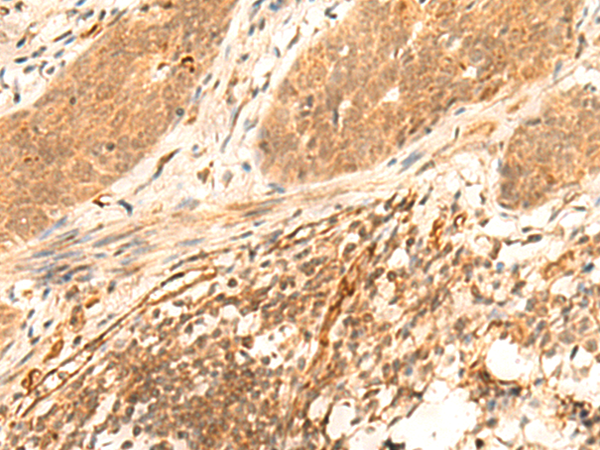

ELISA, IHC |

IHC positive control: |

Human esophagus cancer and Human liver cancer |

IHC Recommend dilution: |

30-150 |